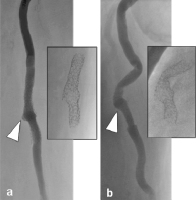

Abbildung 7a-b: Angiographische Darstellung des Bypass-Verlaufs und der Stentarchitektur. (a): Bei Streckung des Oberschenkels, 12-mm-Pseudoaneurysma nach Stentfraktur Typ III (siehe weißer Pfeil), Destruktion der Stentarchitektur (kleines Bild); (b): angiographische Darstellung der Verlaufsveränderungen des Bypasses bei Oberschenkel-Beugung von 80° im Hüftgelenk, Pseudoaneurysma am Übergang zum bindegewebig fixierten Bypass-Segment (weißer Pfeil), korrespondierende Veränderung der Stentarchitektur (kleines Bild).